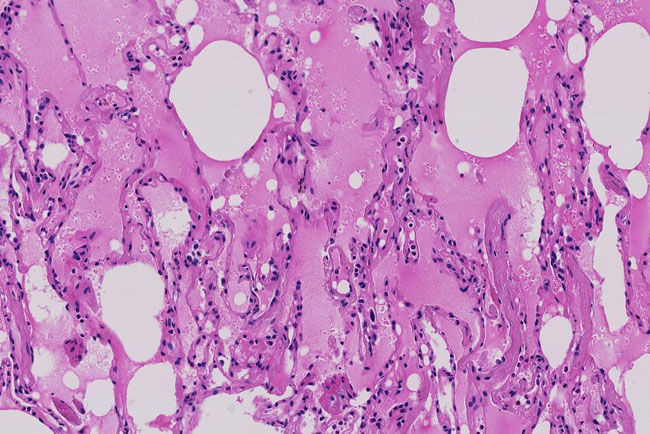

Ảnh chụp tuyến phổi của bệnh nhân đến từ Vũ Hán, cho thấy phế nang chứa đầy chất lỏng màu hồng, sự thay đổi sớm nhất trong phổi của bệnh nhân. Ảnh: Shu-Yuan Xiao.

Sự sưng tấy và dòng lưu thông oxy bị suy yếu có thể khiến những khu vực đó trong phổi chứa đầy chất lỏng, mủ và tế bào chết. Viêm phổi, một dạng nhiễm trùng, có thể xảy ra.